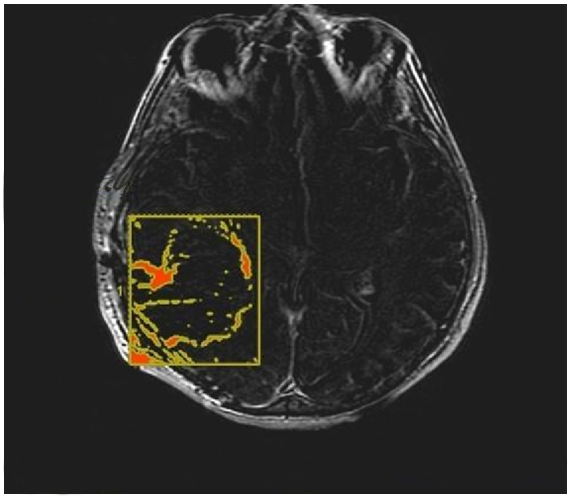

3.2. Quantitative Analysis

- CE-RTV: The median OS value was 19 months for patients with CE-RTV < 5.8 cm3 and 9 months for patients with CE-RTV > 5.8 cm3. The difference was statistically significant (p < 0.004) (Table 2).

- CE-RTV: The median PFS value was 5 months in patients with CE-RTV < 5.8 cm3 and 4 months in patients with CE-RTV > 5.8 cm3. The difference was statistically significant (p = 0.04).